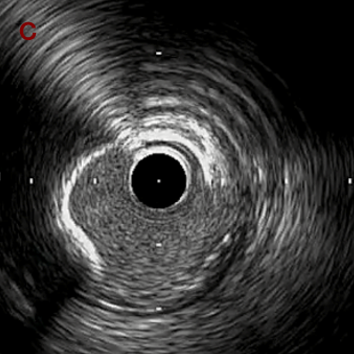

IVUS after OAS high speed 3回

IVUS imaging after high speed 3回

a,b,cはさらに石灰化に食い込み、石灰化量は減少。

それに伴いdではbiasがさらにtentingのIVUS所見にへんかしhigh injury riskと思われた。

引き続き造影で確認してpinpointで引きのOAS high speedを3回さらに追加のためcでIVUSマーキングを行い、その点より引きで赤線のpinpoint OAS high speedを行い、dに関してはinjury回避のためにOASを当てない方針とした。